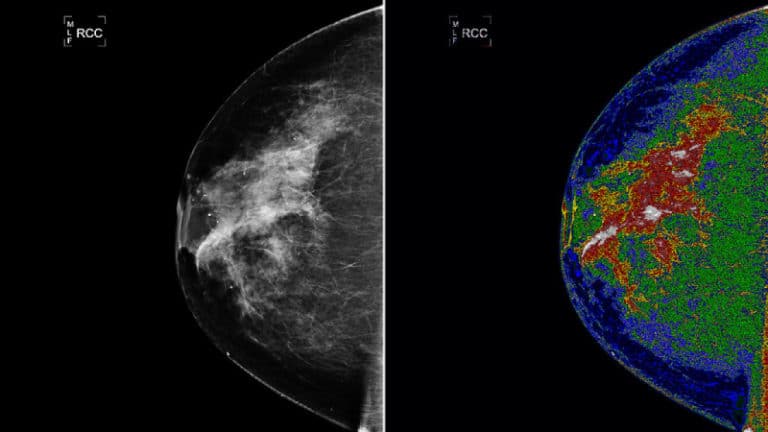

Google AI umí identifikovat rakovinu prsu

Společnost Google vyvíjí umělou inteligenci, která pomůže lékařům s identifikací rakoviny prsu.